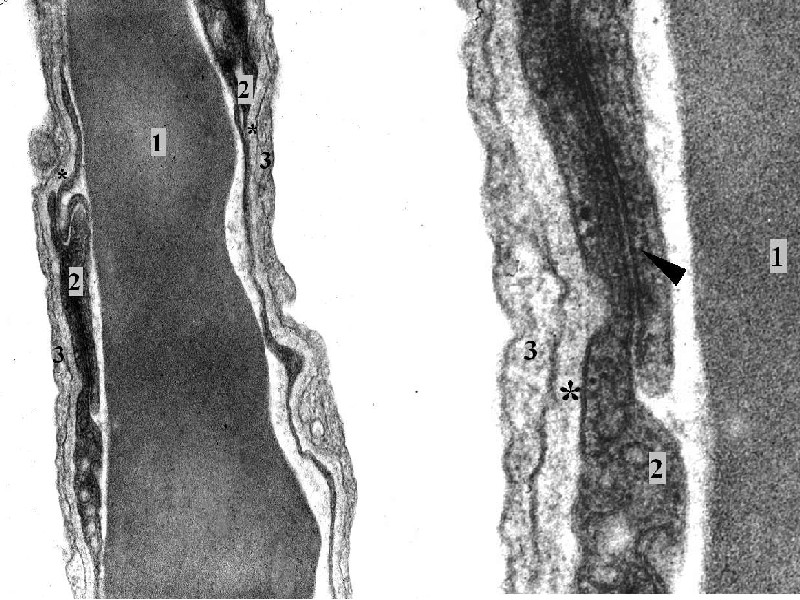

Stěna alveolu v TEM: lumen kapiláry s erytrocytem (1), mezi endotelem kapiláry (2) a cytoplazmou membranózního pneumocytu (3)

společná bazální membrána (*). Šipka ukazuje spojení dvou sousedních entotelových buněk dezmosomem.Vpravo detail.